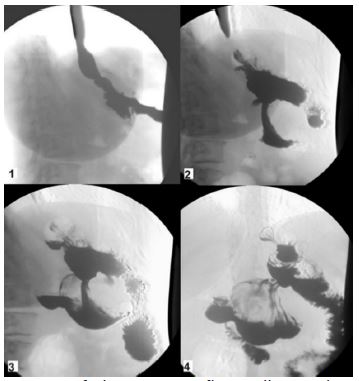

A 57-year-old woman with a history of hypertension, depressive syndrome, right hemithyroidectomy, and several bariatric procedures (Table 1) was hospitalized in the Internal Medical Unit of our clinic for an episode of acute anemia (hemoglobin 79 g/L). She had a well-known iron deficiency anemia that had been present for one year and was being treated with iron carboxymaltose. During the hospitalization, she received transfusions of packed red blood cells, and an Esophagogastroduodenoscopy (EGDS) was performed. It revealed a bulky, vegetant, ulcerated neoformation affecting the angulus/anterior wall of the stomach (Figure 1). The neoformation was sampled with biopsy forceps, and it was histologically defined as a superficially eroded hyperplastic polyp. The Helicobacter Pylori was negative on histological examination (Figure 1).

Figure 1: Endoscopic image of the neoformation affecting the angulus/anterior wall of the stomach.